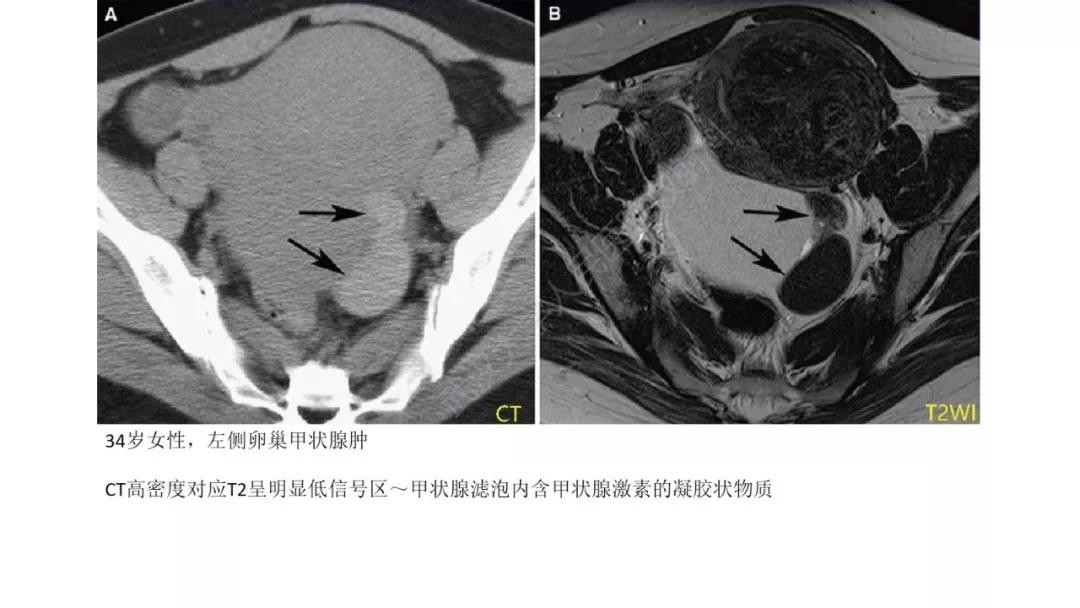

T2WI 低信号病灶:出血、平滑肌、纤维组织、卵巢甲状腺肿(凝胶)